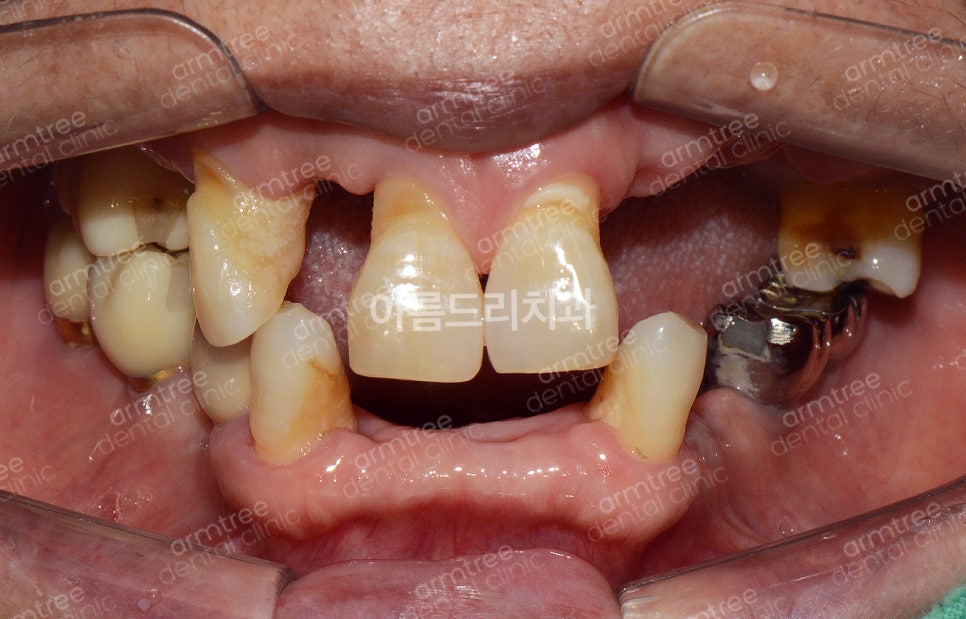

안녕하세요. 아름드리치과 이현정원장입니다. 저 멀리 경상남도에서 찾아오신 환자분입니다. 연세가 조금 있는 여자분이신데 몇 개월 뒤에 발표회를 하는데 예쁘게 보이고 싶다며 멀리서 저를 찾아오셨네요. 저를 찾아오기 전에 흔들리는 상태가 좋지 않은 치아들은 발치를 하셨답니다. 그래서 치아가 듬성듬성 없네요. ...

저를 찾아오기 전에 흔들리는 상태가

좋지 않은 치아들은 발치를 하셨답니다.

그래서 치아가 듬성듬성 없네요.

이렇게 앞니가 듬성듬성 없이 지내는 걸

듬성 듬성 발치가 되어 있습니다. 빼면서 바로 임플란트를 심었다면 좋았을텐데 아쉽네요

발치하지 않은 남은 치아들도 상태가 좋지 않았고

어금니는 이미 여러개의 임플란트를 심었습니다.

그런데 오른쪽 어금니가 씹히질 않네요ㅠㅠ

앞니 2개가 툭~ 튀어나와 있습니다.

바로 옆치아가 발치됐고 뼈가 흡수돼서

상대적으로 더 튀어나와 보이네요.

환자분께 여쭤보니 젊었을 때부터

입이 튀어나와보였다고 하십니다.